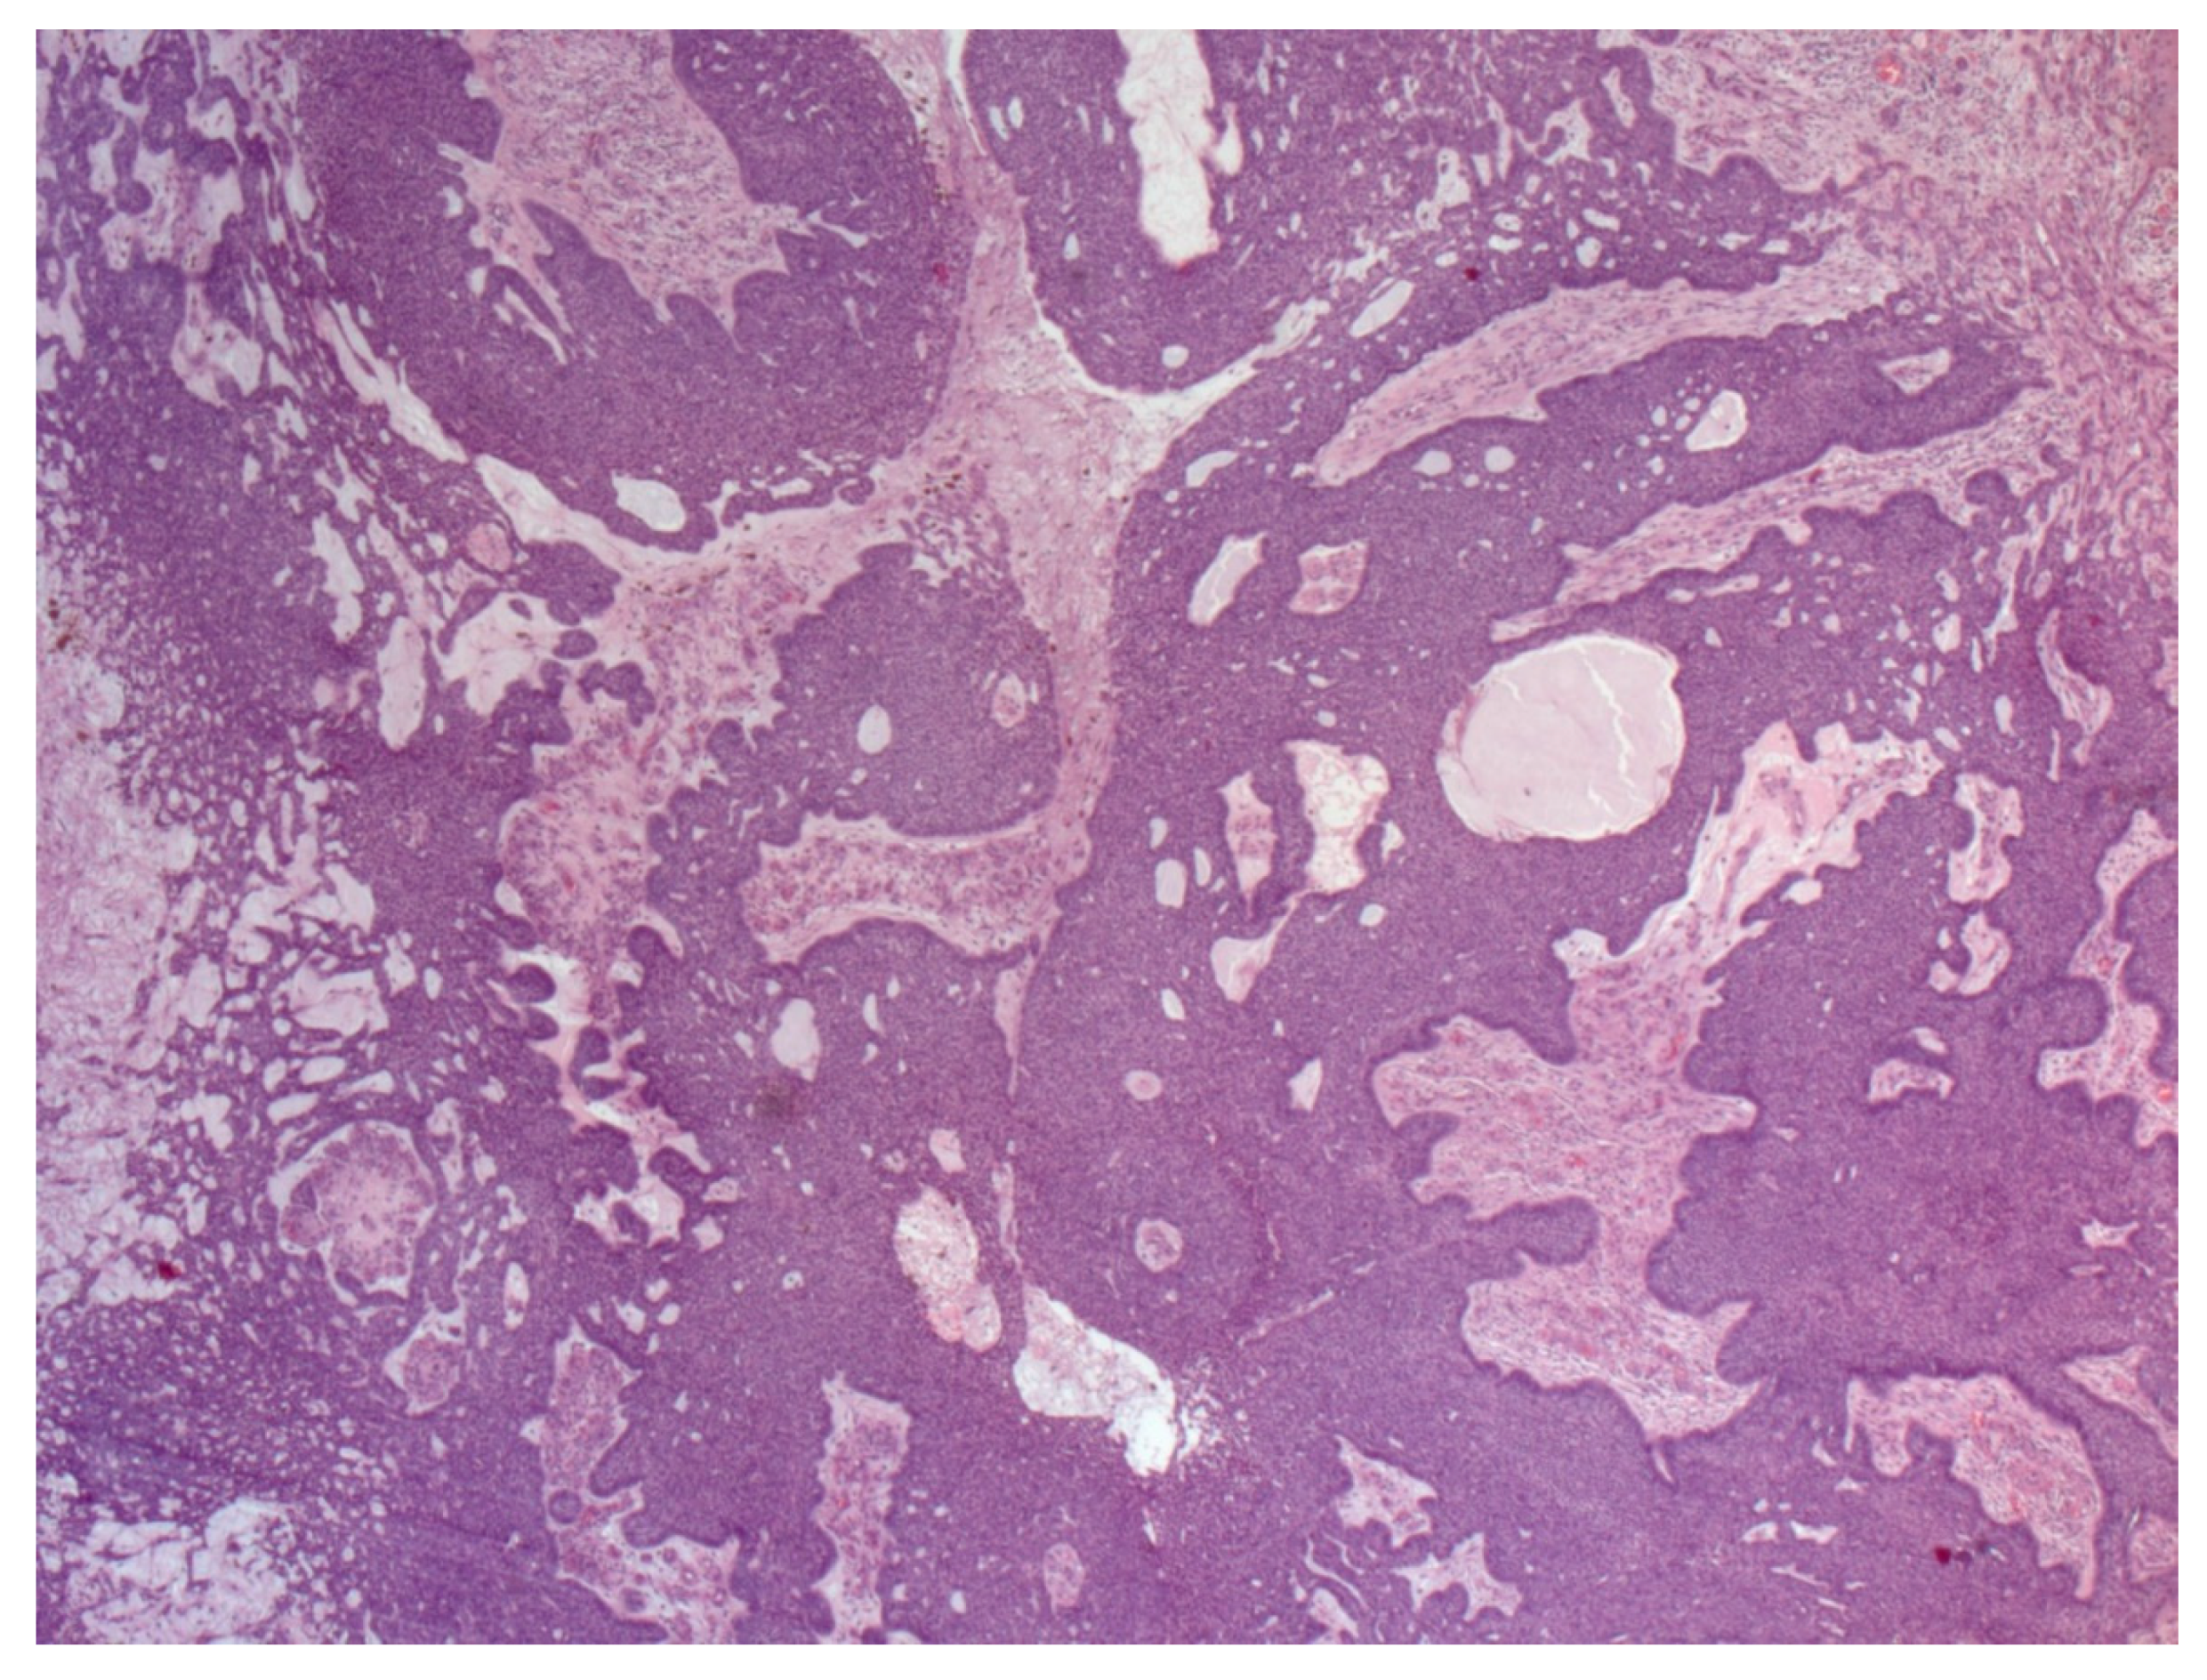

4. Histopathological Features of BCC

- Paolino, G.; Donati, M.; Didona, D.; Mercuri, S.R.; Cantisani, C. Histology of Non-Melanoma Skin Cancers: An Update. Biomedicines 2017, 5, 71. [Google Scholar] [CrossRef] [Green Version]